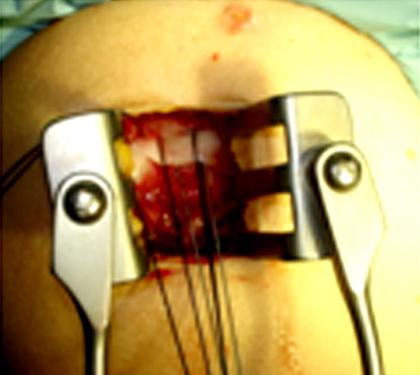

การรักษาโดยการผ่าตัดผ่านกล้องไหล่ ถือเป็นมาตรฐานการรักษาโรคของข้อไหล่ที่ยอมรับกันทั่วโลก นอกจากสามารถให้การวินิจฉัยแล้วยังเป็นการรักษาในคราวเดียวกัน กรณีที่เหมาะสมต่อการผ่าตัดส่องกล้องข้อไหล่ คือโรคของข้อไหล่ที่รักษาด้วยวิธีอนุรักษ์นิยมอย่างเต็มที่แล้ว ซึ่งประกอบด้วย การรับประทานยาแก้ปวด เช่น พาราเซตามอล, ยาลดอาการอักเสบที่ไม่ใช่สเตียรอยด์ และยาคลายกล้ามเนื้อ ร่วมกับกายภาพบำบัดอย่างเต็มที่แล้วไม่ได้ผล เป็นเวลาอย่างน้อย 3-6 เดือน จึงพิจารณานำวีธีการผ่าตัดผ่านกล้องมารักษา ซึ่งจะทำการเปิดแผลขนาด 0.5 - 1 ซ.ม. ประมาณ 2-3 แผล เพื่อใส่กล้องขนาดประมาณ 4 มิลลิเมตร ใส่น้ำเกลือเข้าไปในข้อเพื่อขยายพื้นที่ในการผ่าตัด และใส่อุปกรณ์การผ่าตัดเพื่อทำการรักษา พบว่าผลการรักษาไม่แตกต่างจากการรักษาโดยการเปิดแผล แต่กลับฟื้นตัวได้เร็วขึ้น

ตัวอย่างการผ่าตัดผ่านกล้องรักษากระดูกงอกทับเส้นเอ็นหัวไหล่